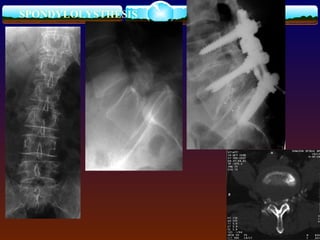

SPONDYLOLYSTHESIS

Imaging Studies  lumbarAP, lateral, and oblique views.  lateral flexion and extension,MRI  Meyerding’s system for grading: Grade 1 is 25%, Grade 2 is 50%, Grade 3 is 75%, Grade 4 is 100% displacement , GradeV --spondyloptosis